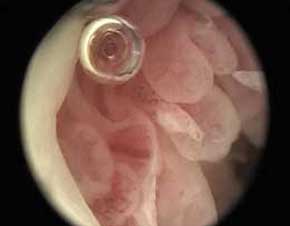

- 骨关节炎检查

针刀镜技术针刀镜显示骨性关节炎患者关节腔内大量横络产生